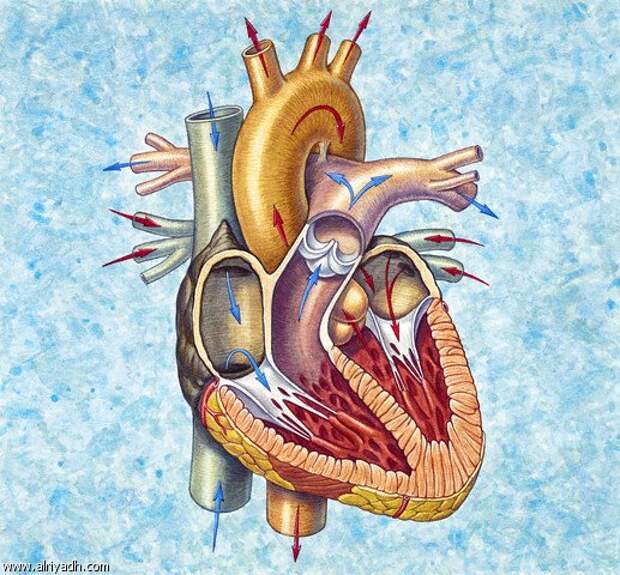

Фотографии и информация о приобретенных пороках сердца